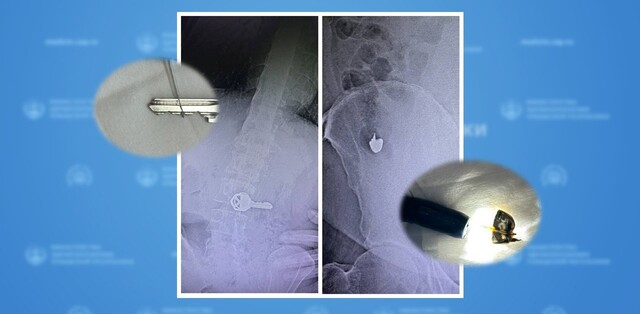

Шупашкарти тухтӑрсем икӗ пациента операци туса вӗсен пурнӑҫне ҫӑлнӑ. Вӗсен хырӑмлӑхӗпе пыршӑлӑхӗнчен шӑл коронки тата алӑк уҫҫи кӑларнӑ.

Хулари 1-мӗш клиника больницин эндоскопи уйрӑмне пӗр кунра 2 арҫынна илсе килнӗ. Тӗрӗсленӗ хыҫҫӑн вӗсен организмӗнче ют япаласем пуррине палӑртнӑ. Иккӗшне те ҫийӗнчех операци тунӑ. Пӗрин хырӑмлӑхӗнчен тимӗр уҫӑ кӑларнӑ, тепри хулӑн пыршӑлӑхӗнче шӑл коронки пулнӑ.